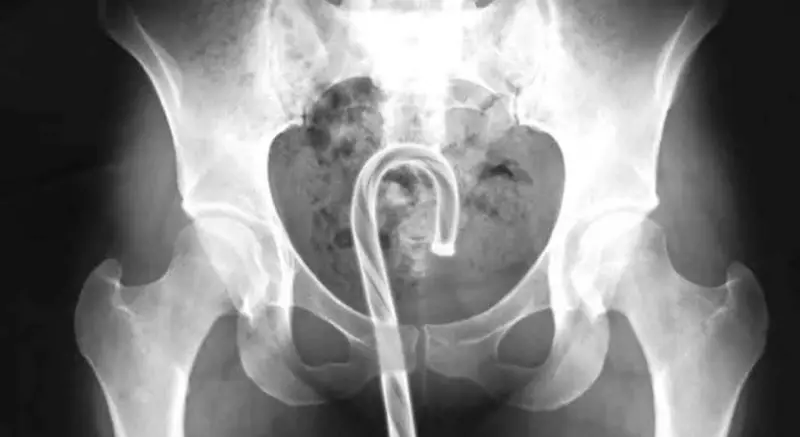

Emergency room physicians consistently report that many situations become far more severe because patients try to solve the problem themselves before seeking professional medical help. Scans and X-rays often reveal secondary objects like tweezers, coat hangers, or other improvised tools that were used in failed extraction attempts. Clinicians warn that these efforts significantly raise the risk of internal tears, serious bleeding, and dangerous infections. The advice repeated in numerous case studies is clear and straightforward: seeking early medical intervention is always safer than risky improvisation.

Medical professionals note that objects without a flared base are especially prone to getting stuck, as a vacuum-like suction can form once the item moves beyond reach.